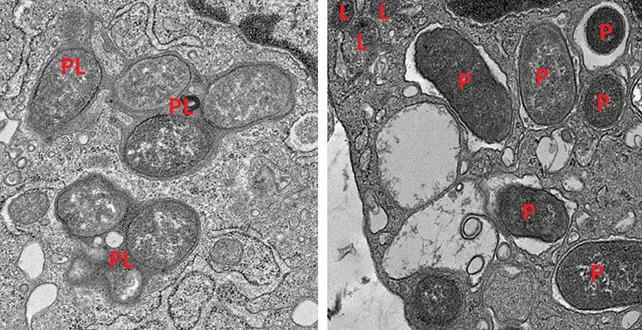

Macrophages expressing girdin (left) can neutralize pathogens by forming phagolysosomes (PL). Macrophages that lack girdin (right) can’t form phagolysosomes, allowing pathogens to evade detection. (Katkar et al., J. Clin. Invest., 2025)

The researchers describe macrophages in the gut as being on opposing teams, increasing or reducing inflammation. (Katkar et al., J. Clin. Invest., 2025)